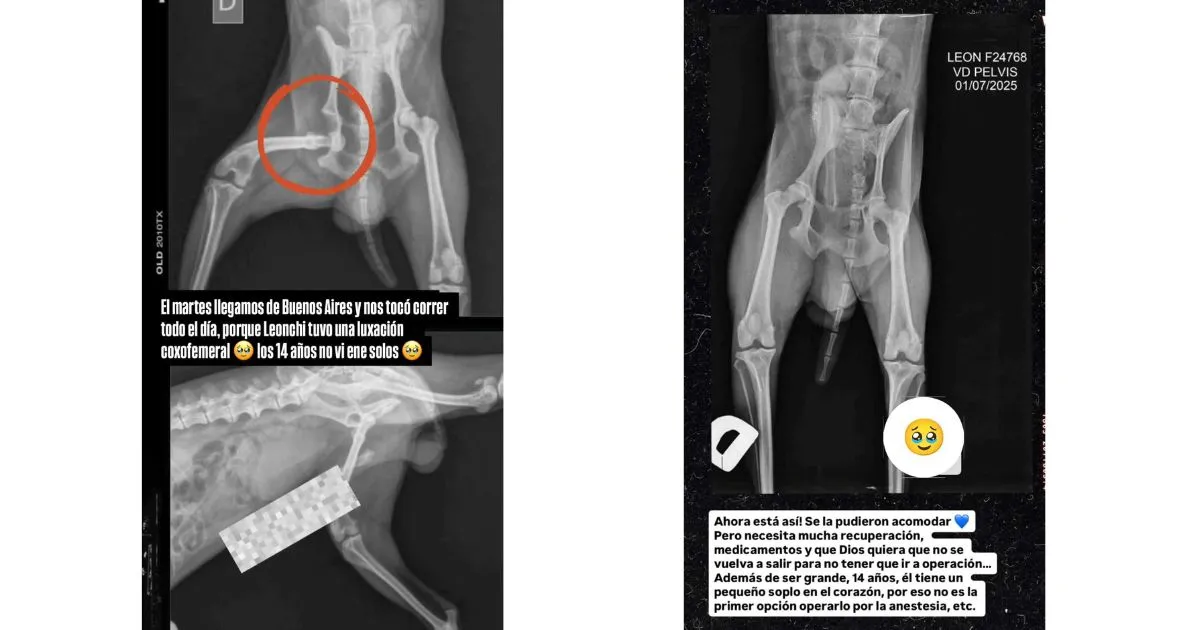

La influencer publicó la foto de una radiografía de su mascota, donde se ve la lesión que sufrió en una de sus extremidades.

"El martes llegamos de Buenos Aires y nos tocó correr todo el día, porque Leonchi tuvo una luxación coxofemoral. Los 14 años no vienen solos", escribió sobre la imagen.

En una siguiente radiografía, mostró que le pudieron acomodar la pata, pero "necesita mucha recuperación y medicamentos".

"Que Dios quiera que no se vuelva a salir para no tener que ir a operación. Además de ser grande (14 años), tiene un pequeño soplo al corazón, por eso no es primera opción operarlo por la anestesia", explicó Euge.